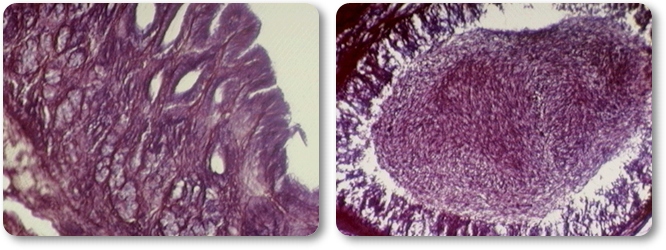

Tall transversal d'artèria:

L'estructura de la paret de les artèries ha de permetre suportar les ones de pressió produ‹des per la sang bombejada pel cor. Per tant, una artèria típica té tres capes ben diferenciades: La túnica interior de les artèries està formada per teixit conjuntiu llis, que permet el pas fluid de la sang. La túnica mitjana és gruixuda i conté membranes elàstiques separades per fibres musculars llises. Dóna fortalesa i capacitat de variació del diàmetre. La túnica externa és una beina conjuntiva, que reforça el conjunt.

Tall transversal de vena:

Per raó que la pressió sanguínia és molt menor que a les artèries, la paret de la vena és mes prima que la de les artèries, i no és elàstica, manté sempre el mateix diàmetre. La capa intermèdia té molt de teixit conjuntiu, menys elàstic que en les artèries. En algunes venes es poden trobar vàlvules que impedeixen retrocedir a la sang, encara que són molt més abundants als vasos del sistema limfàtic.